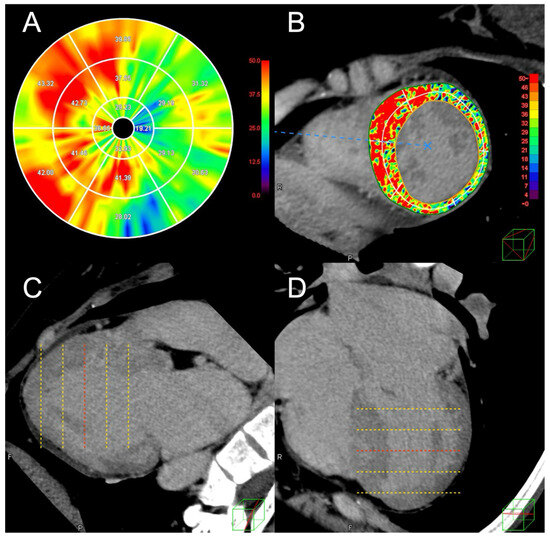

With the advancement of fractional flow reserve (FFR) derived from computed tomography (FFRCT), virtual stenting technology has gradually developed. This study investigated the performance of virtual stenting based on FFRCT in predicting post-percuta...